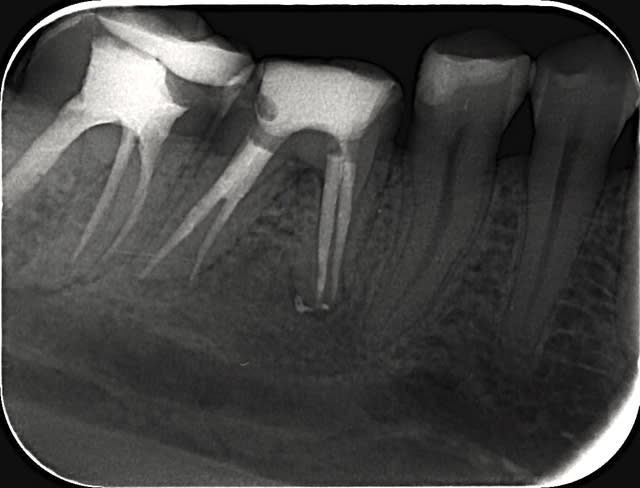

Apres 8 mois

Fig.5,6